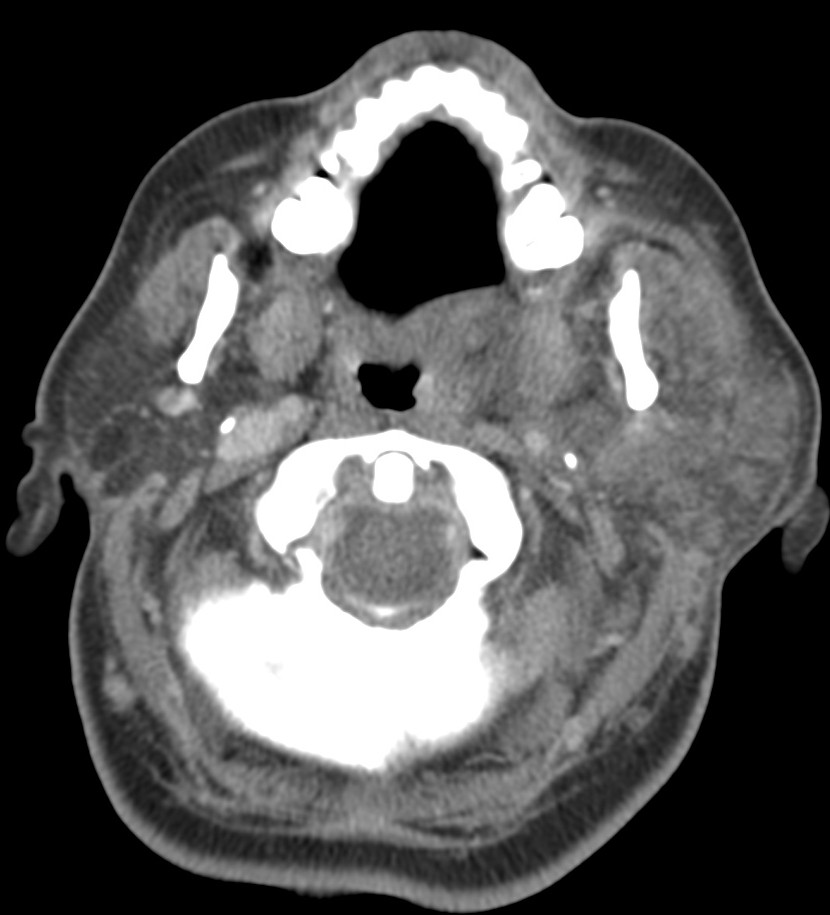

ESPACIO SUBLINGUAL Y SUBMANDIBULAR. ANGINA DE LUDWING:

Espacio sublingual:

Se sitúa inferior a la porción móvil de la lengua pero superior y medial al músculo milohioideo = Colecciones en esta localización son las denominadas sublinguales (las reconstrucciones coronales y sagitales son fundamentales). Contiene además a la glándula sublingual y una pequeña porción del aspecto superior de la glándula submandibular. Igual que en el espacio submandibular, las infecciones se manifiestan clínicamente por tumefacción, dolor, rubicundez y aumento de temperatura cervical. La mayoría son de origen dentario:

- Las que afectan a los dientes anteriores suelen limitarse al espacio sublingual, ya que sus raíces se quedan superior al milohiodeo.

- Las infecciones del 2º y 3º molar se suelen localizar en el espacio submandibular, ya que sus raíces se sitúan inferior a la inserción del milohioideo en la cara medial de la mandíbula (ver a continuación).

Espacio submandibular:

El espacio submandibular se sitúa inferior y lateral al músculo milohioideo. Es posterior al borde libre del milohioideo y comunica con el espacio sublingual (ver foto arriba). Contiene además la glándula submandibular, ganglios y a veces pueden localizarse quistes branquiales.

- Las infecciones del 2º y 3º molar se suelen localizar aquí. También pueden ser debidas a las supuración de adenopatías.

- Las infecciones de la glándula submandibular pueden confundirse con las de la parótida.

- Se produce aumento de tamaño, hiperdensidad e infiltración de la grasa adyacente. Cuando esto ocurre, se debe examinar el conducto de Wharton en busca de posibles cálculos.

- Otra forma de manifestación la constituye el flemón, con o sin celulitis y/o miositis, en estos casos se visualizan como masas hiperatenuadas, de bordes mal delimitados, con o sin engrosamiento e hiperatenuación de la musculatura, la piel y el tejido celular subcutáneo adyacentes.

Angina de Ludwing:

No es un absceso, es una celulitis multiespacial ya que afecta al suelo de la boca y los espacios sublingual y submandibular. Se manifiesta clínicamente por dolor, hinchazón, disfagia, fiebre y elevación de la lengua, puede asociar crepitación si se deben a microrganismos anaerobios. En la TC con contraste se observa:

- Realce y edema difuso de los componentes del suelo de la boca.

- Debe determinarse si existe colección susceptible de drenaje, permeabilidad de la vía aérea y presencia de aire secundario al crecimiento de microorganismos anaerobios.

- La infección causa elevación y desplazamiento de la lengua que puede cerrar la vía aérea (debe tenerse en cuenta a la hora de manejar estos pacientes antes de realizar la prueba).